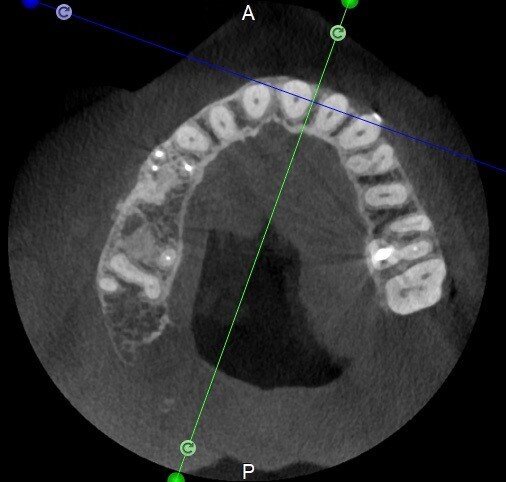

The case with which I would like to start my clinical review is a perfect example of how difficult it is to establish the origin of the patient’s symptoms on the basis of an intraoral radiograph alone. Not only does the 2D study fail to establish with certainty the presence of a lesion, but more importantly, it is impossible to establish the size, morphology and type of the lesion. An analysis of the 3D imaging, however, provides a clear picture of the clinical situation: the coronal and sagittal slices revealed the presence of a large lesion extending from the apex of the mesial root of this molar to the furcation, while the axial slices allow us to conduct a precise analysis of the endodontic anatomy and, in particular, the shape of the mesial root, which in this case was fused with the palatine root. A full overview of the case can, therefore, guide the decision-making process and direct the treatment plan towards a specific type of treatment (Figs. 1–4).